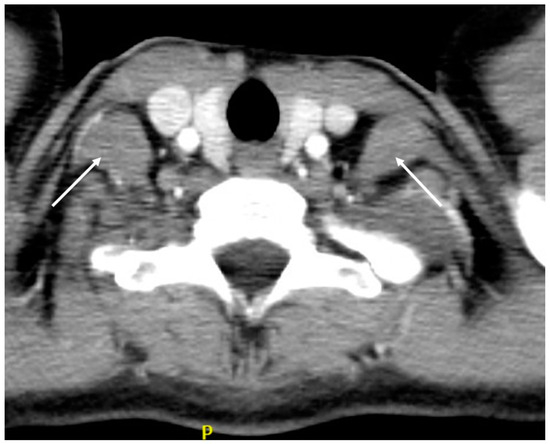

4.3. Computed Tomography (CT)